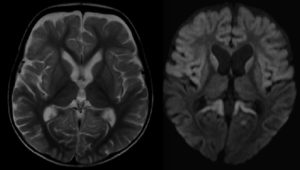

Encefalopatía aguda

La encefalopatía aguda se caracteriza por un mal funcionamiento del sistema nervioso central. Los síntomas más comunes que se presentan son la pérdida de memoria, convulsiones, un estado de coma e incluso la muerte. Los síntomas de la encefalitis pueden aparecer durante los primeros tres días de la infección viral y comienza por fiebre alta.

A medida que se agudiza el virus en el niño se lesionan diversas estructuras cerebrales como:

- Cuerpo calloso: Comunica los hemisferios izquierdo y derecho por lo que, debido al virus, los niños pueden llegar a presentar tanto cambios emocionales como conductuales debido a un daño estructural.

- Tálamo: Integra la información sensorial de entrada y salida. El virus produce problemas motrices durante y después de la enfermedad. Algunas de estas alteraciones engloban la función de coordinación y ejecución de movimientos debido a la progresión del virus a la corteza cerebral.

- Cerebelo y médula espinal: Procesan todos lo movimientos finos mediante vías de entrada y salida. Cuando los niños sobreviven al virus, en su forma agresiva, suelen tener dificultades en tareas motrices.